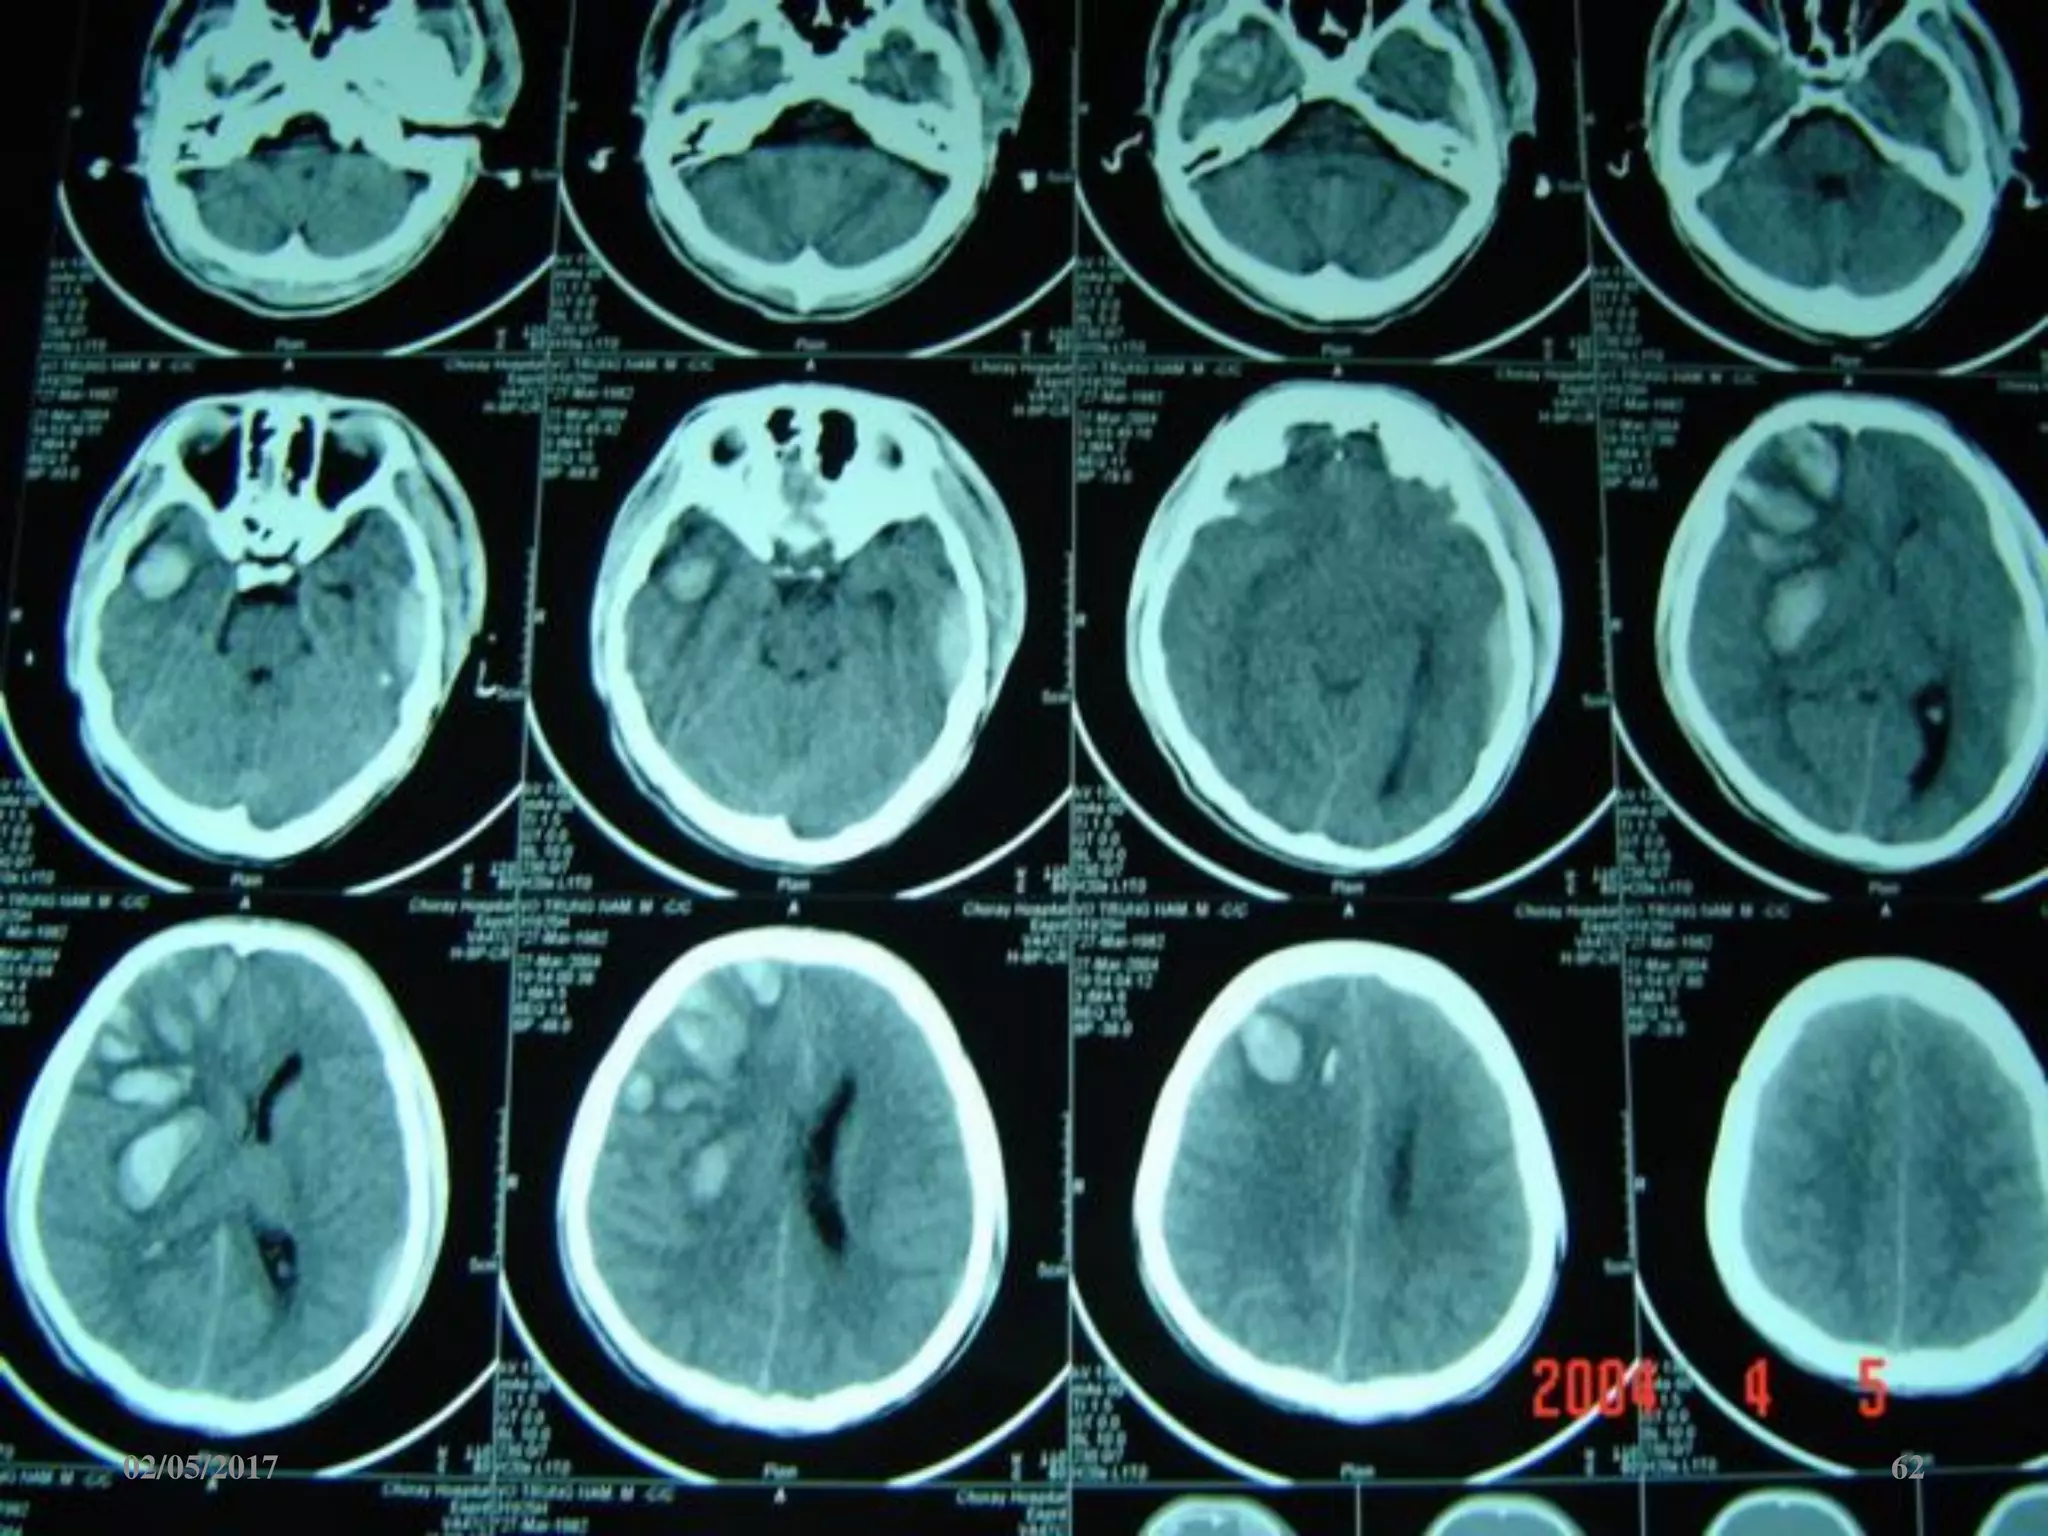

Máu tụ trong não

• Vị trí: trán, thái

dương, đỉnh, chẩm.

• Hình ảnh tăng đậm

độ trong tổ chức não